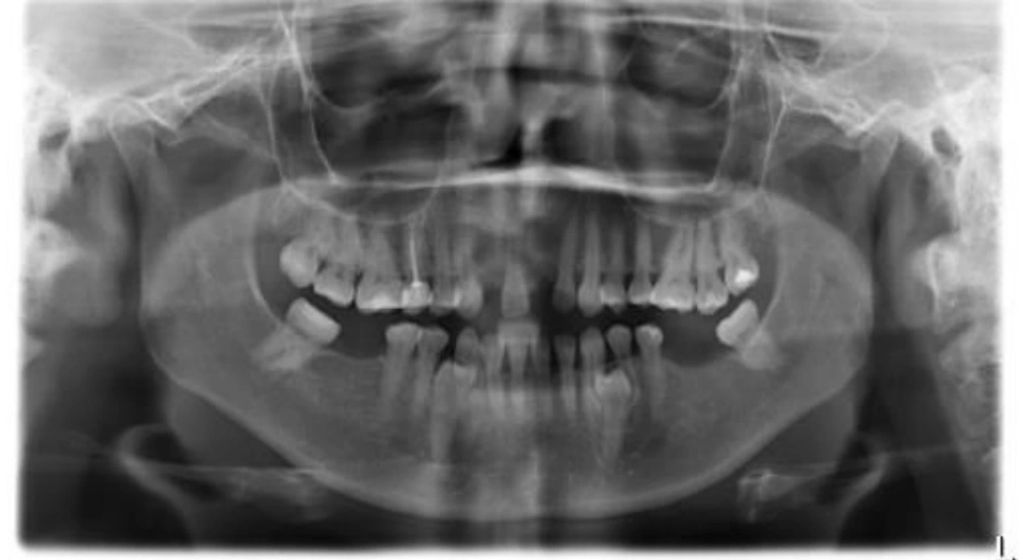

En la Rx. Panorámica de diagnóstico observamos ausencia de los diente 12 y 21 con una atrofia ósea severa, razón por la cual, ya le habían dicho al paciente en otras clínicas odontológicas, que necesitaba injertos óseos y un tiempo de tratamiento de 1 año.

Observamos la Rx. Panorámica de control donde podemos apreciar los dos implantes en posición, según la planificación realizada para este caso de alta complejidad.